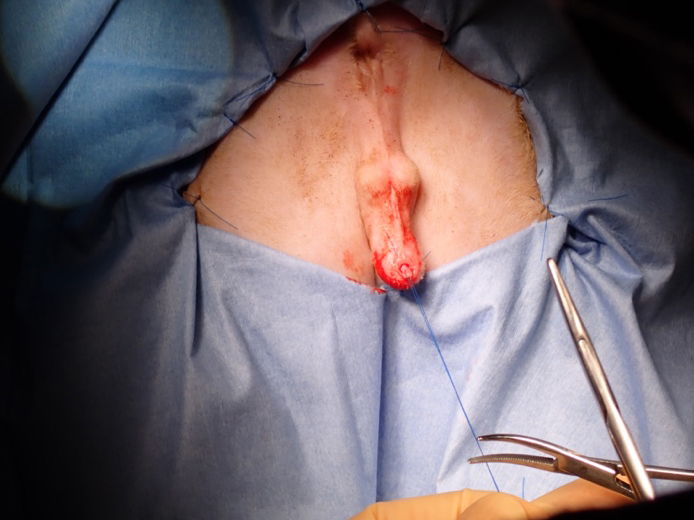

手術中の体位

手術中の様子